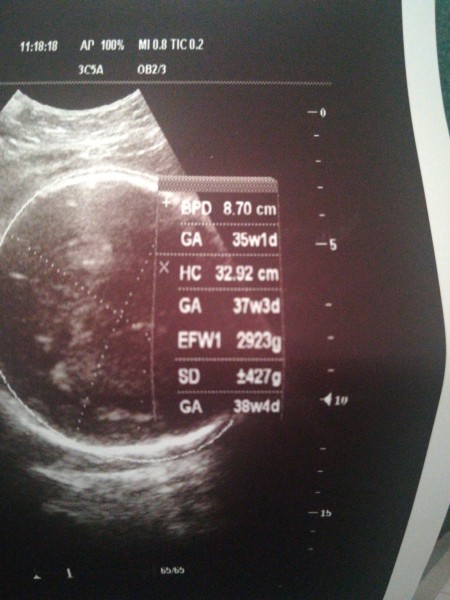

Ultrason Terimleri Hamilelikte Olcumler Crl Bpd Ne Demek Buyurken

En Detayli Ultrason Terimleri Rehberi Mynet Trend